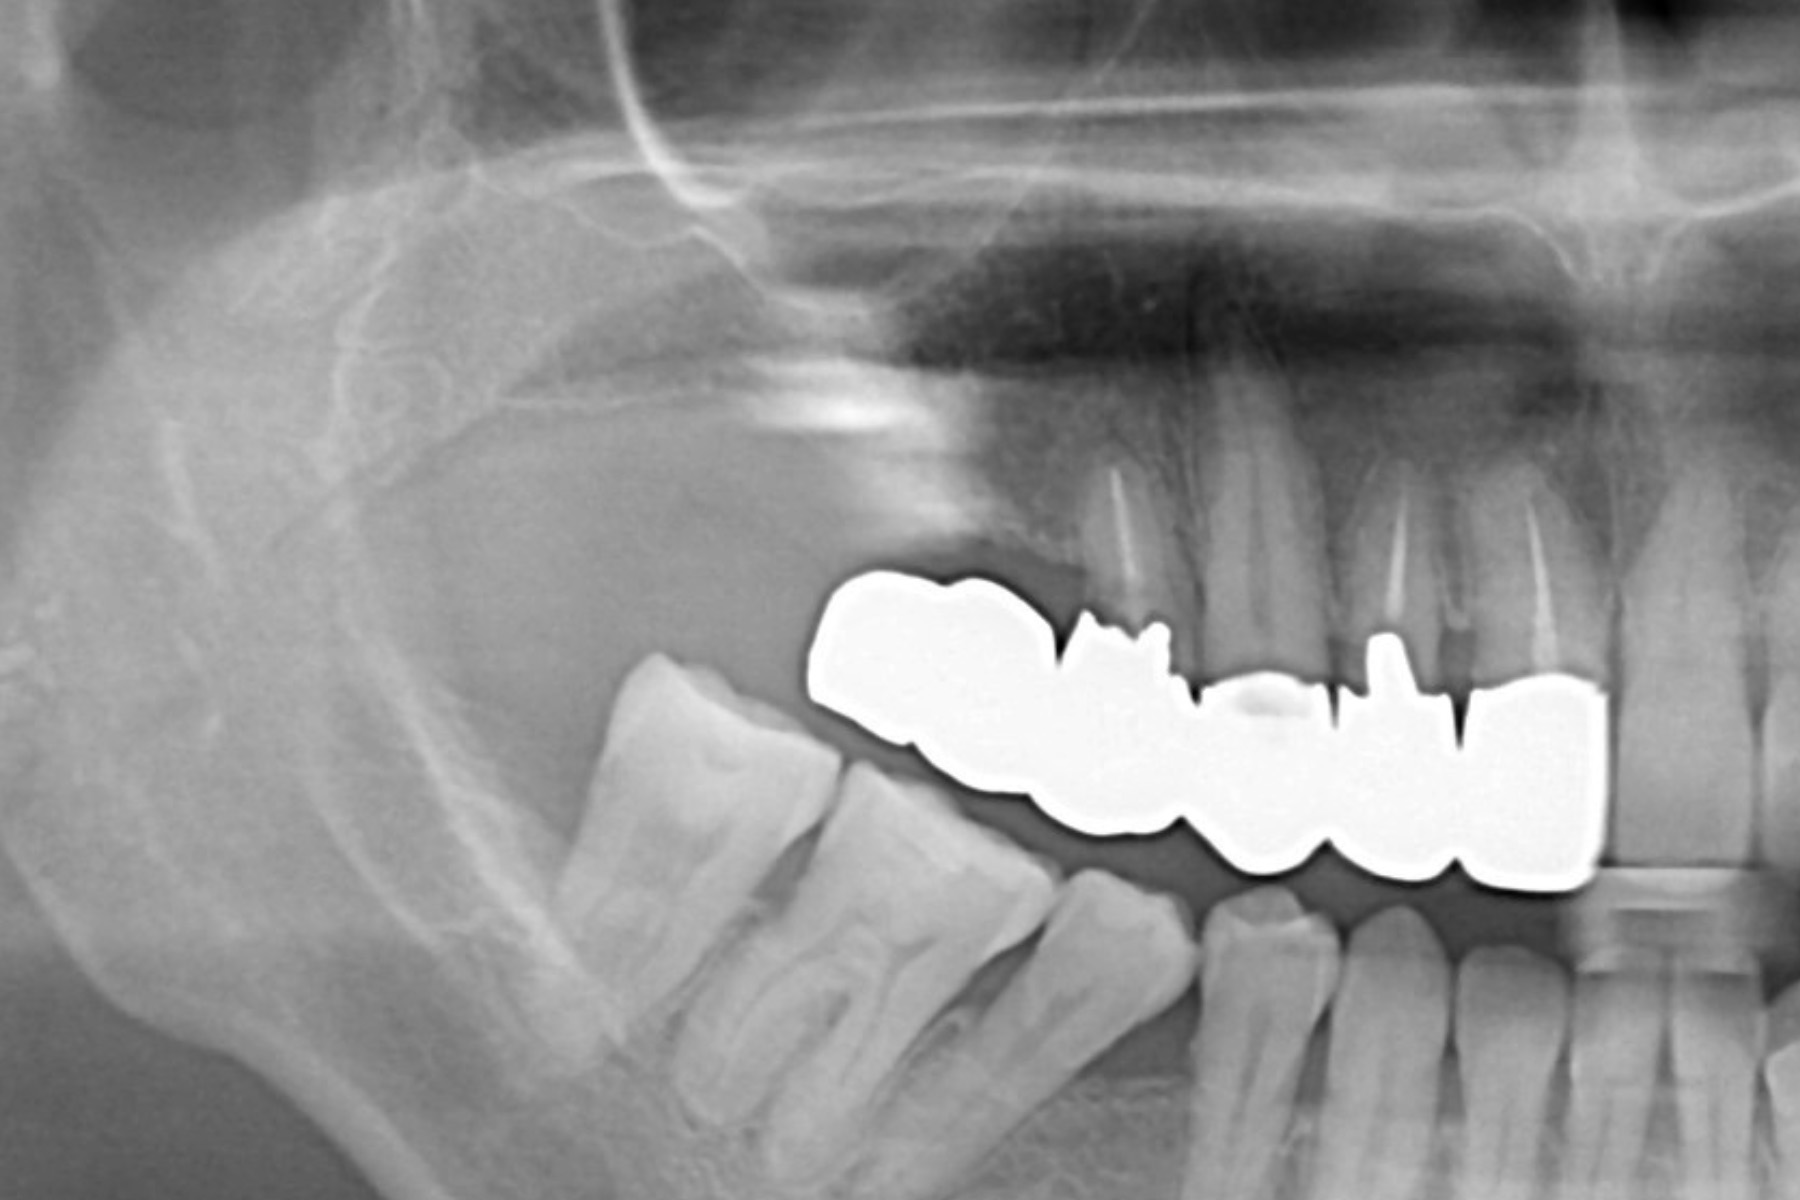

CASE17:骨造成手術(サイナスリフト)

症例

CASE17